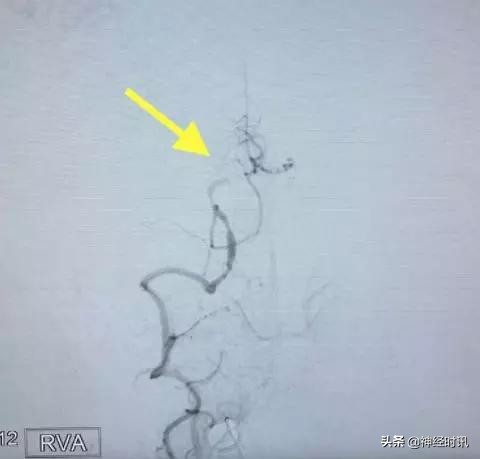

病例2(下图)是一个反复头晕发作的病例,通过脑血管造影我们发现患者的右侧椎动脉已经闭塞(黄箭),左侧椎动脉颅内段95%的狭窄(红箭),这种狭窄本身不难处理,但是,同侧粗大的小脑后下动脉发自于狭窄段,而且其起始段已经狭窄呈线样(小白箭),可谓藕断丝连!

点击图片可查看大图详情